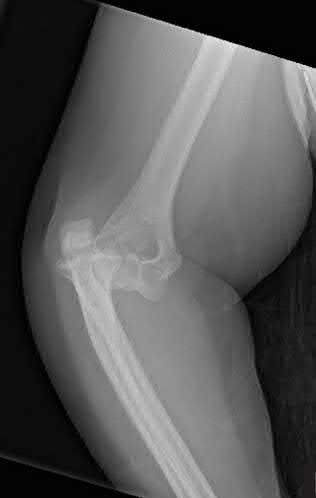

A 15-year-old boy is diagnosed with high-grade intramedullary osteosarcoma of the distal femur.

What is the single most important prognostic factor for his overall survival?

Explanation

In osteosarcoma, the single most important prognostic factor for survival is whether metastatic disease is present at the time of diagnosis. For patients presenting with localized disease, the percentage of tumor necrosis following neoadjuvant chemotherapy (>90% necrosis indicates a good response) becomes the most important prognostic factor.